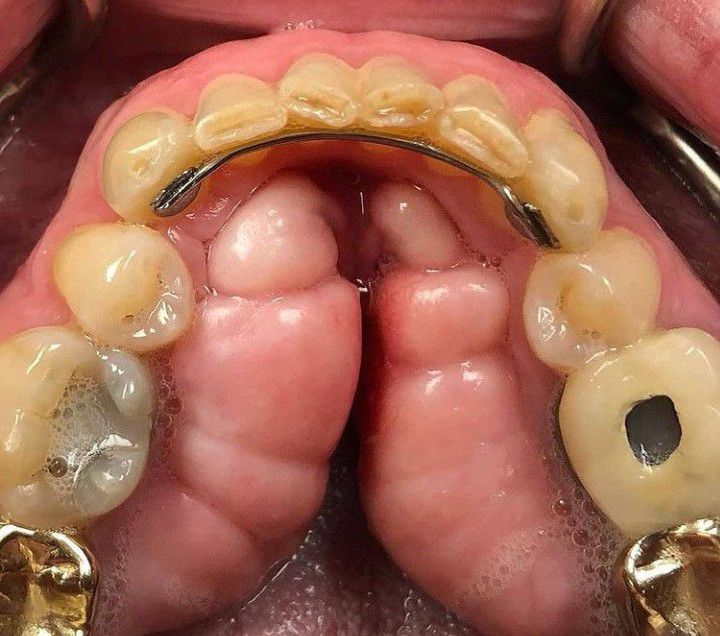

Torus mandibularis or Mandibular tori is a bony growth in the mandible along the surface of the tongue. Mandibular tori are usually present near the premolars and above the location of the mylohyoid muscle's attachment to the mandible. In 90% of cases, they are found on both the left and right sides. FACTORS: Factors responsible for mandibular tori include: Trauma or injury to the mouth's interior Jawbone stress due to teeth grinding and clenching Diet influences, such as vitamin deficiencies, fish consumption, and calcium-rich diets. Age and sex Genetics TREATMENT: The treatment is only recommended in case of complication or severity, otherwise dental professionals usually don't recommend any treatment. The complications arises if the torus: Becomes inflamed when scraped while eating or engaging in other activities (like having dental X-rays) Begins to interfere with basic daily functions (eating and speaking) Hinders the placement of braces or a prosthesis Grow to the point where they touch in the middle of the mouth Cause other oral health problems In case of Scraped tori, bacteria in the mouth is decreased which causes the area to heal. This is easily done by cleansing the injured area with a germ-killing fluoride toothpaste or rinse. If the tori must be extracted, it is performed by a maxillofacial surgeon to remove the bony growth.The surgery has the same risks as any other surgery. Credits: https://www.instagram.com/p/CLeZ4kiJe1R/?igshid=48undzc44dvf https://www.colgate.com/en-us/oral-health/mouth-and-teeth-anatomy/what-are-mandibular-tori